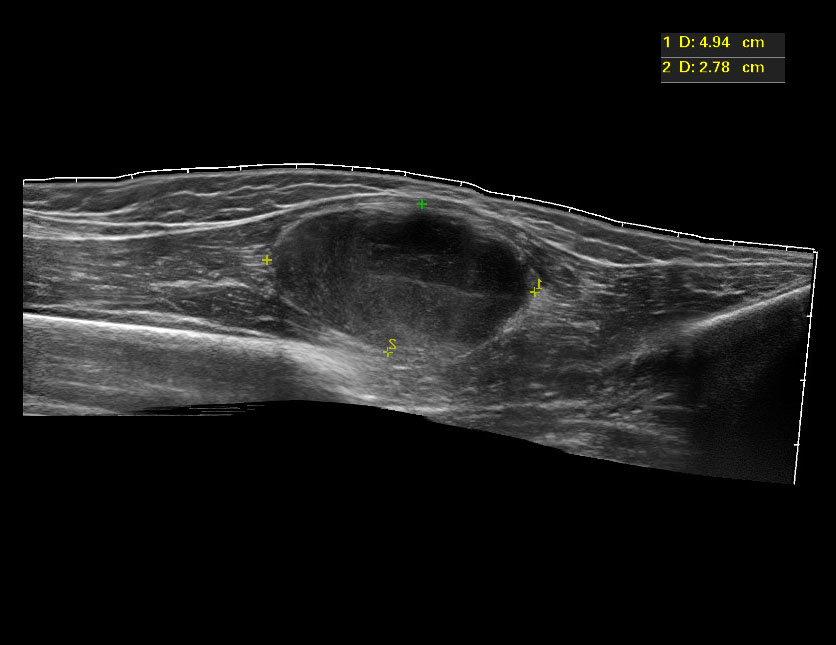

Девочка 12 лет, быстрорастущее образование на бедре.

20160125_091615_5.jpg

C49 Злокачественное новообразование других типов соединительной и мягких тканей

C49.2 Соединительной и мягких тканей нижней конечности, включая тазобедренную область

Низкодифференцированная злокачественная опухоль периферического нерва.